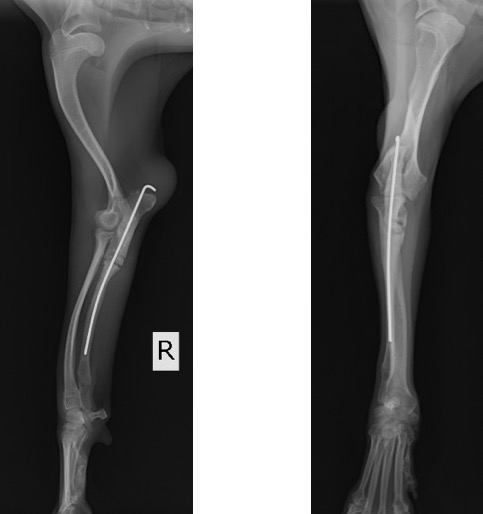

術後の側面像と頭尾側像 (前例と同じく髄内ピンとしてK-wireを刺入したのちに切り取った骨片を破砕し、骨切部分へ再移植しました。)